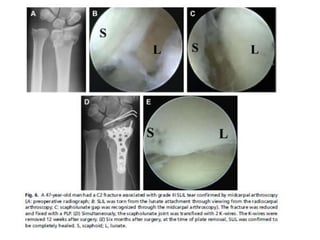

Artroscopia

• También puede ayudar en la reducción de las pequeñas fracturas

articulares desplazadas, tales como en una impactación perforadora

de matriz, proporcionando una mejor visualización de la superficie

articular.

• Además, en la configuración de radiocubital distal inestabilidad de la

articulación que persiste después de la fijación placa volar.

Artroscopia • También puedeayudar en la reducción de las pequeñas fracturas articulares desplazadas, tales como en una impactación perforadora de matriz, proporcionando una mejor visualización de la superficie articular. • Además, en la configuración de radiocubital distal inestabilidad de la articulación que persiste después de la fijación placa volar.